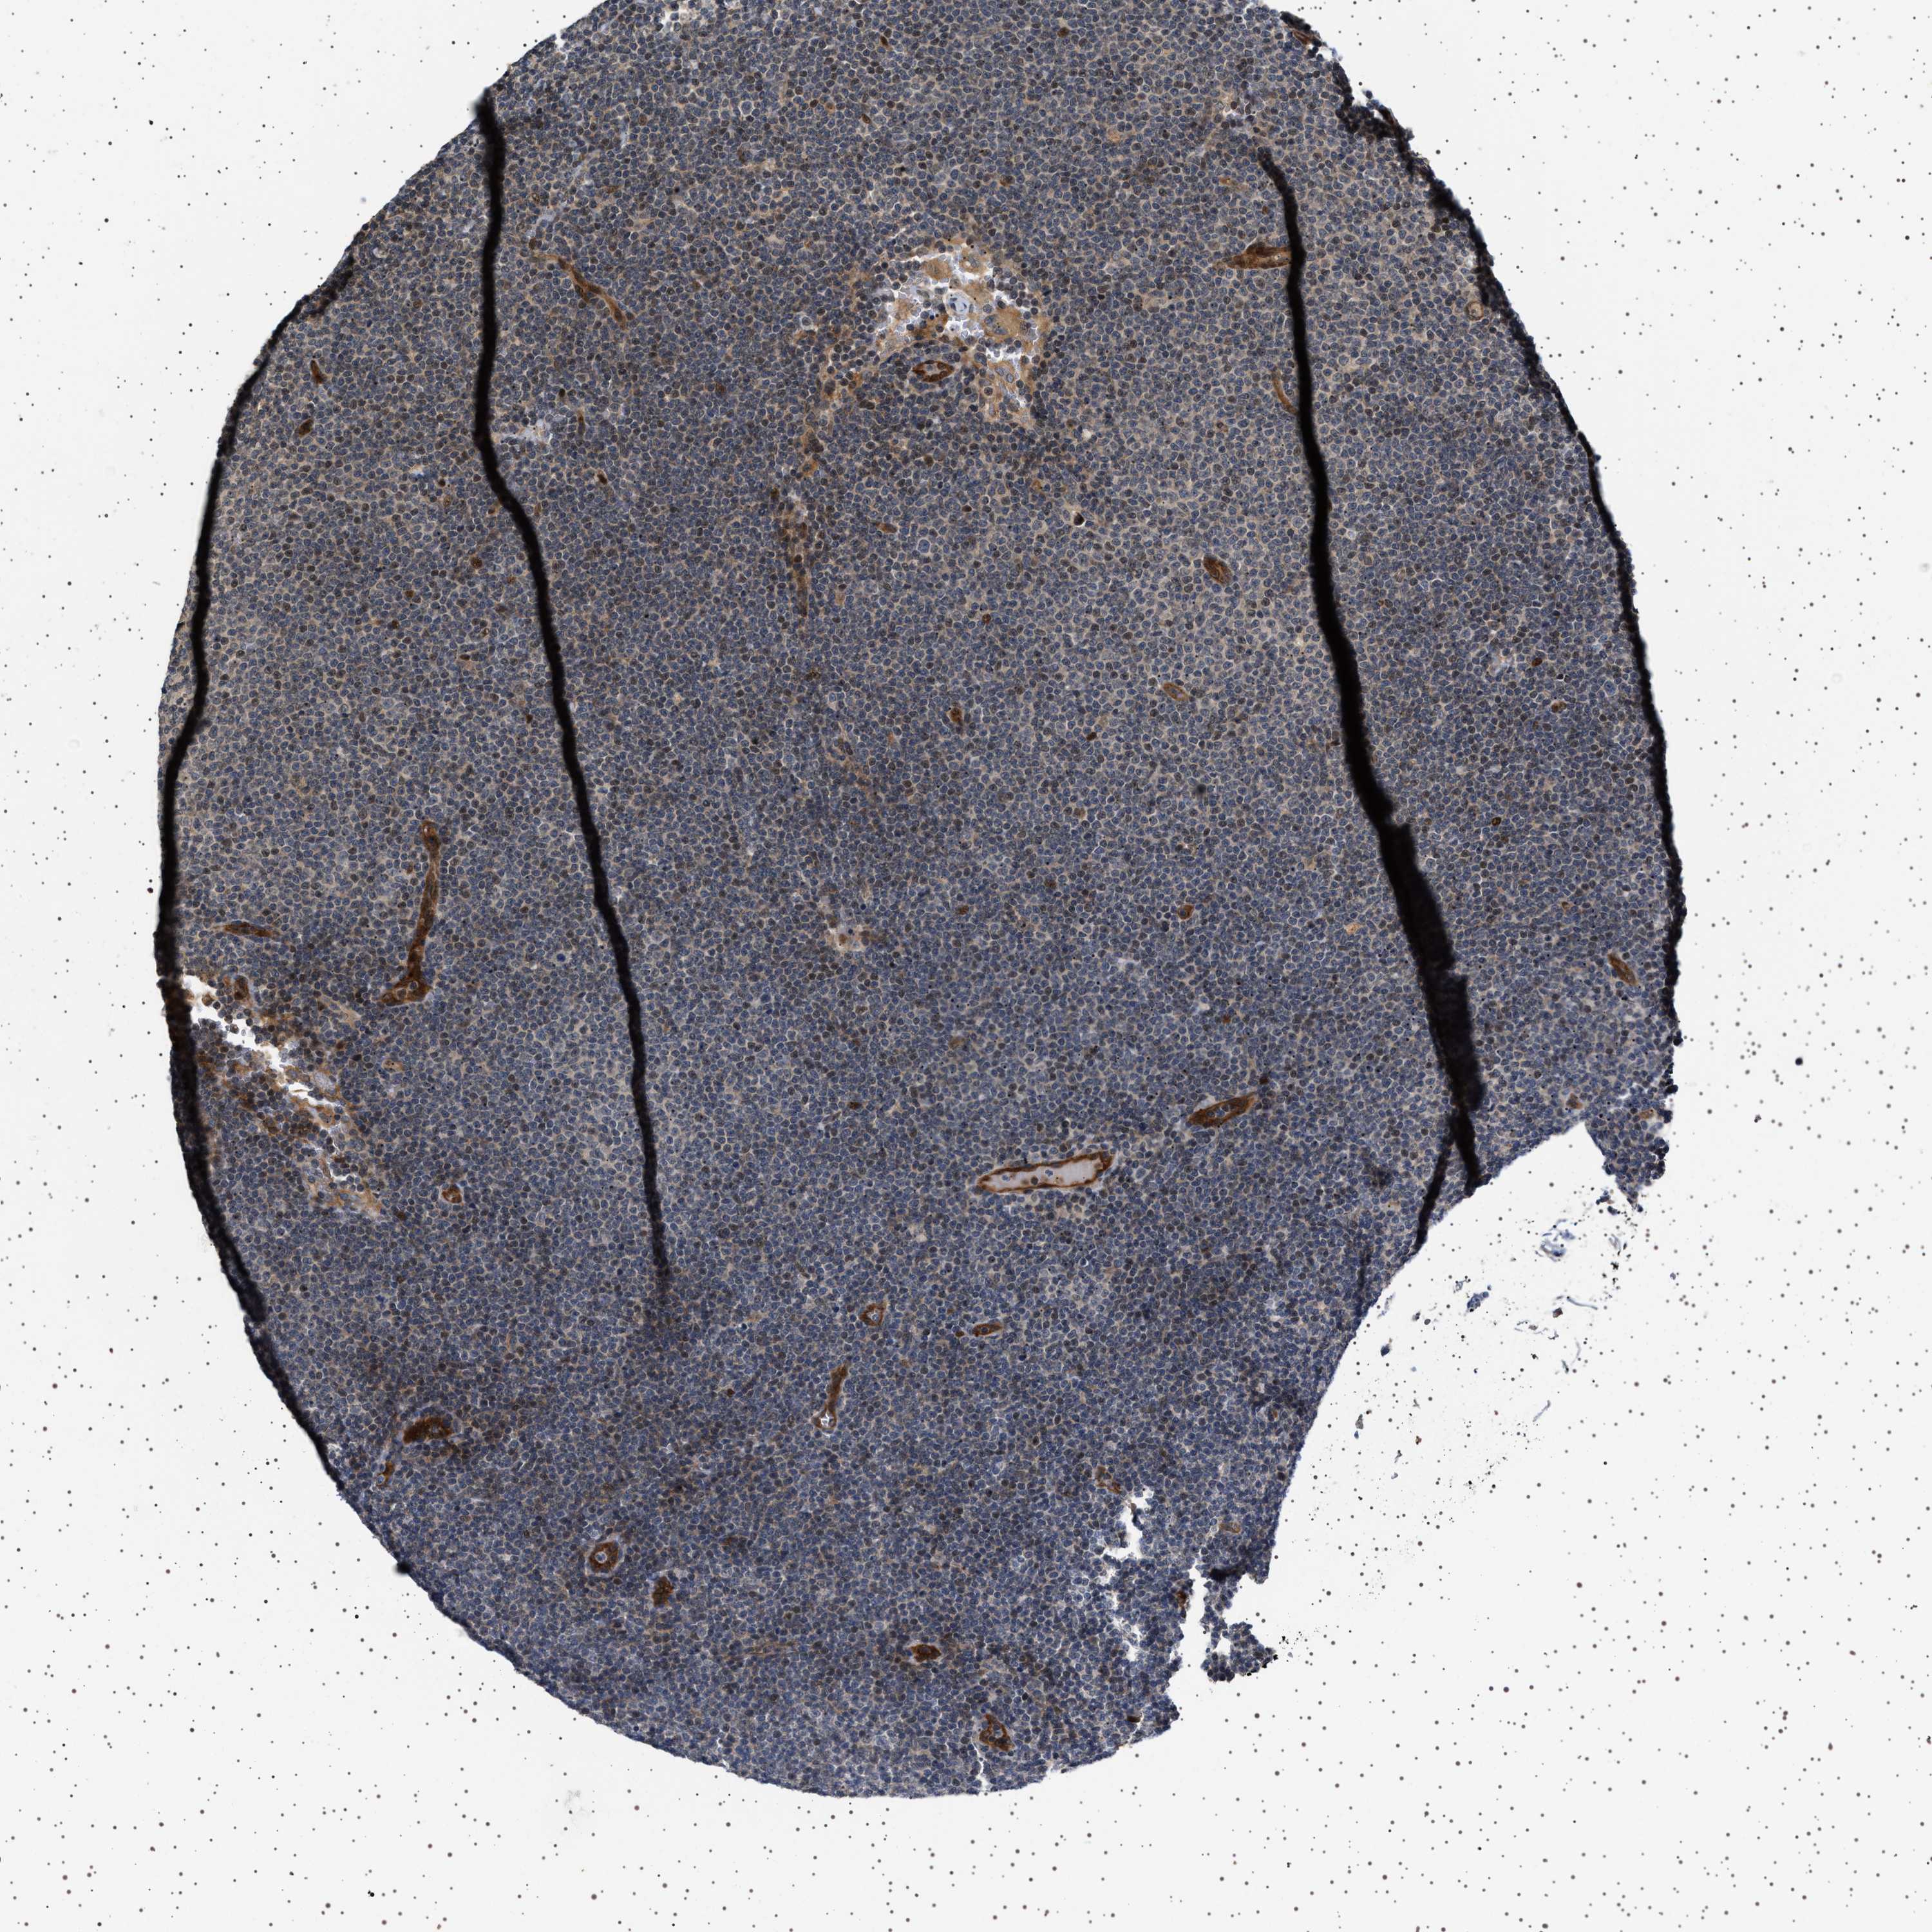

LYMPHOMA - Protein expressioni

A mouse-over function shows sample information and annotation data. Click on an image to view it in a full screen mode. Samples can be filtered based on level of antibody staining by selecting one or several of the following categories: high, medium, low and not detected. The assay and annotation is described here.

Each image is clickable and will lead to virtual microscopy that enables deeper exploration of all samples and also displays staining intensity scores, fraction scores and subcellular localization as well as patient and tissue information for each sample.

Antibody HPA018493

Hodgkin's disease, NOS

Malignant lymphoma, non-Hodgkin's type, High grade

Malignant lymphoma, non-Hodgkin's type, Low grade